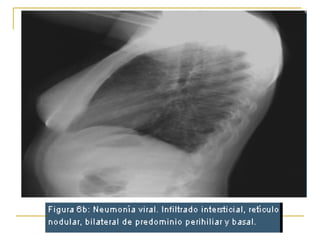

Patrones radiográficos en neumonía viral MAS FRECUENTE Infiltrados peribronquiales parahiliares (bronquitis) FRECUENTE Infiltrados parahiliares bilaterales con atelectasia RARO Patrón intersticial reticulo-nodular FRECUENTE EN NIÑOS MENORES DE 2 AÑOS Aumento del volumen pulmonar, sin infiltrados (Bronquiolitis) Tomado de Swischuk L. In: emergency Imaging of the acutely III or Injured Child. Slipknot Williams & Wilkins. 2000.

Infiltrado intersticial retículo nodular bilateral de predominio perihiliar y basal